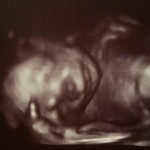

Foto de ultrassom na semana 22